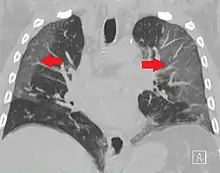

Ground-glass opacity (GGO) is a finding seen on chest x-ray (radiograph) or computed tomography (CT) imaging of the lungs. It is typically defined as an area of hazy opacification (x-ray) or increased attenuation (CT) due to air displacement by fluid, airway collapse, fibrosis, or a neoplastic process.[1] When a substance other than air fills an area of the lung it increases that area's density. On both x-ray and CT, this appears more grey or hazy as opposed to the normally dark-appearing lungs. Although it can sometimes be seen in normal lungs, common pathologic causes include infections, interstitial lung disease, and pulmonary edema.[2][3]

Ground-glass opacity is most often used to describe findings in high-resolution CT imaging of the thorax, although it is also used when describing chest radiographs. In CT, the term refers to one or multiple areas of increased attenuation (density) without concealment of the pulmonary vasculature. This appears more grey, as opposed to the normally dark-appearing (air-filled) lung on CT imaging. In chest radiographs, the term refers to one or multiple areas in which the normally darker-appearing (air-filled) lung appears more opaque, hazy, or cloudy. Ground-glass opacity is in contrast to consolidation, in which the pulmonary vascular markings are obscured.[3][5] GGO can be used to describe both focal and diffuse areas of increased density.[5] Subtypes of GGOs include diffuse, nodular, centrilobular, mosaic, crazy paving, halo sign, and reversed halo sign.[6]

Diffuse

The diffuse pattern typically refers to GGOs in multiple lobes of one or both lungs. Broadly, a diffuse pattern of GGO can be caused by displacement of air with fluid, inflammatory debris, or fibrosis. Cardiogenic pulmonary edema and ARDS are common causes of a fluid-filled lung. Diffuse alveolar hemorrhage is a rarer cause of diffuse GGO seen in some types of vasculitis, autoimmune conditions, and bleeding disorders.[6]

Inflammation and fibrosis can also cause diffuse GGOs. Pneumocystis pneumonia, an infection typically seen in immunocompromised (e.g. patients with AIDS) or immunosuppressed individuals, is a classic cause of diffuse GGOs. Many viral pneumonias and idiopathic interstitial pneumonias can also lead to a diffuse GGO pattern. Radiation pneumonitis, a side effect of pulmonary radiation therapy, can lead to pulmonary fibrosis and diffuse GGOs.[6]